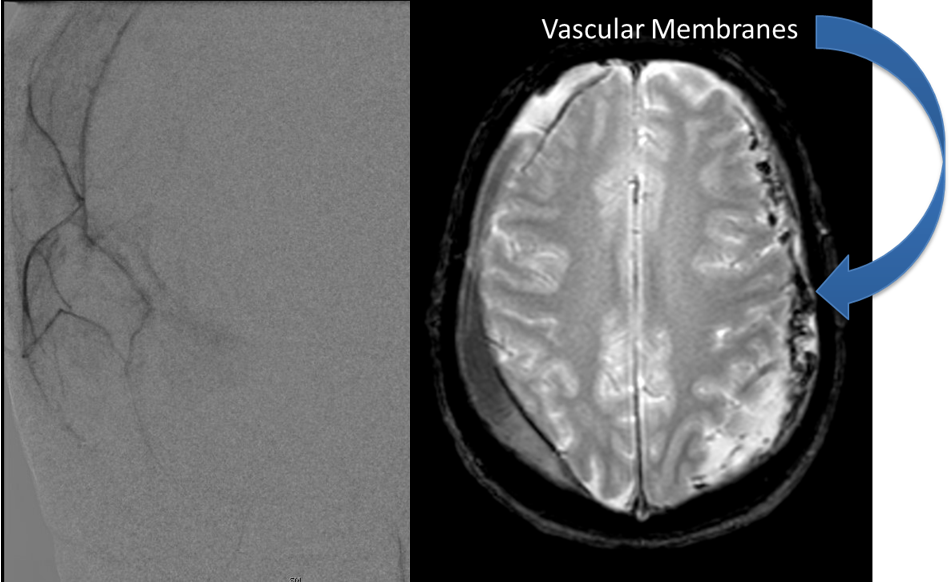

Endovascular:

CME:

Direct Carotid Cavernous Fistula (CCF)

Author: Jonathan L. Brisman M.D., F.A.C.S., Read More!